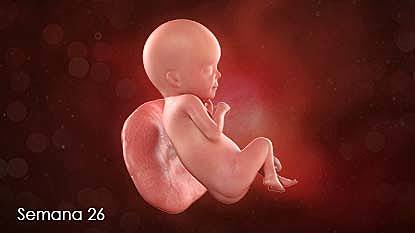

26

Semana 26

-Las cejas y las pestañas están bien formadas.

-Todas las partes de los ojos están desarrolladas.

-El feto presenta el reflejo prensil y de sobresalto.

-Se comienzan a formar las huellas de la piel plantar y de la piel palmar.

-Se forman los alvéolos pulmonares.

Desarrolla todo lo relacionado con los ojos, huellas de los pies y pulmones funcionando completamente